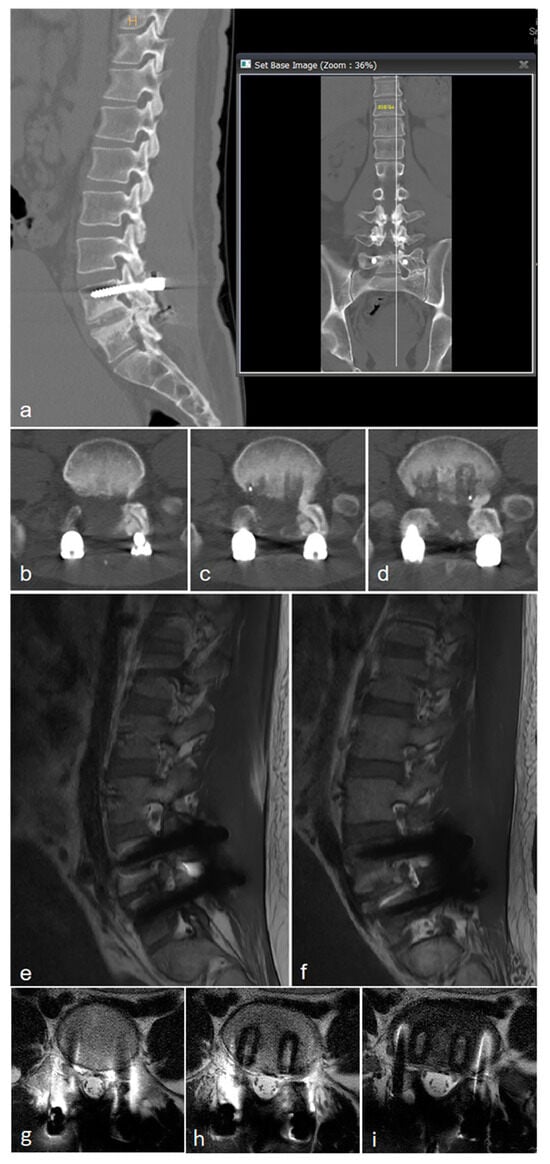

2.1. Case 1

2.2. Case 2